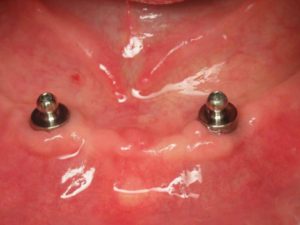

- Boutons-pression à la mandibule

La revue de la littérature scientifique montre que la technique de boutons-pression est à présent considérée comme une option de choix quand il s’agit d’améliorer la rétention d’une prothèse amovible complète à la mandibule, avec comme principaux avantages la simplicité d’exécution et la maintenance réduite par rapport aux barres.

Par ailleurs, l’élaboration d’une prothèse sur boutons-pression est relativement simple et peu onéreuse.

La prothèse existante peut être conservée si elle est encore satisfaisante, dans la mesure où le couloir prothétique correspond à l’émergence des implants (ce qui est presque toujours le cas).

L’entretien par le patient est facile et les problèmes gingivaux (inflammation, prolifération) sont inexistants.

Les réinterventions sont aisées (changement des anneaux de rétention ou des boutons-pression, rebasage).

La rétention d’une prothèse sur boutons-pression est aussi efficace que celle procurée par une barre.